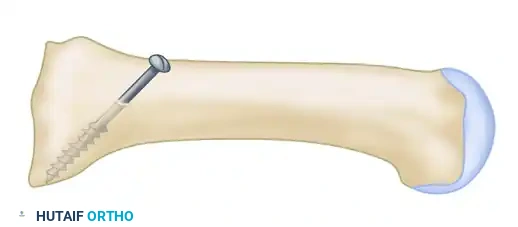

- Pre-drilling the Glide Hole: Crucial Step. Drill a 3.5-mm glide hole at the 2-cm mark (1 cm distal to the planned osteotomy) in the center of the metatarsal shaft, directing it proximally. Performing this before the osteotomy ensures absolute stability during drilling.

- Executing the Osteotomy: Use a specialized curved crescentic saw blade. The convexity of the blade must face distally.

- Biomechanics: A distally convex cut prevents overcorrection of the intermetatarsal angle and minimizes shortening of the first ray.

- Score the dorsal cortex, then gently rock the blade medially and laterally. Ensure the lateral aspect of the blade exits the lateral cortex cleanly. The medial cortex can be finished with a small osteotome if necessary.

- Place a centering device ("golf tee" or "mushroom" guide) into the pre-drilled 3.5-mm glide hole.

- Drill the proximal fragment with a 2.0-mm or 2.5-mm drill bit.

- Tap the proximal fragment with a 4.0-mm tap.

- Insert a 4.0-mm fully threaded cancellous screw (typically 26 mm in length).

Clinical Pearl: Countersinking is Mandatory

Use a countersink in the dorsal glide hole before inserting the screw. This gently removes cortical bone from the distal hole, allowing the screw head to sit flush. If omitted, the screw head will abut the dorsal cortex during the final turns, acting as a wedge that will inevitably fracture the intervening cortical bone bridge, leading to catastrophic loss of fixation.